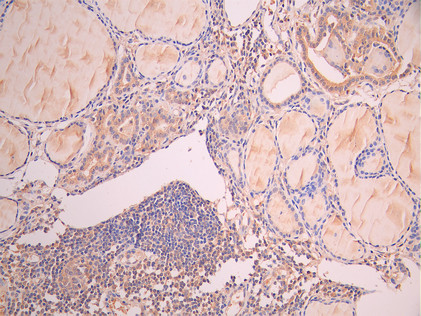

IHC image of CSB-RA859102MA1HU diluted at 1:50 and staining in paraffin-embedded human thyroid tissue performed on a Leica BondTM system. After dewaxing and hydration, antigen retrieval was mediated by high pressure in a citrate buffer (pH 6.0). Section was blocked with 10% normal goat serum 30min at RT. Then primary antibody (1% BSA) was incubated at 4°C overnight. The primary is detected by a Anti-Human lgG, Fcy Fragment Specific labeled by HRP and visualized using 0.05% DAB.